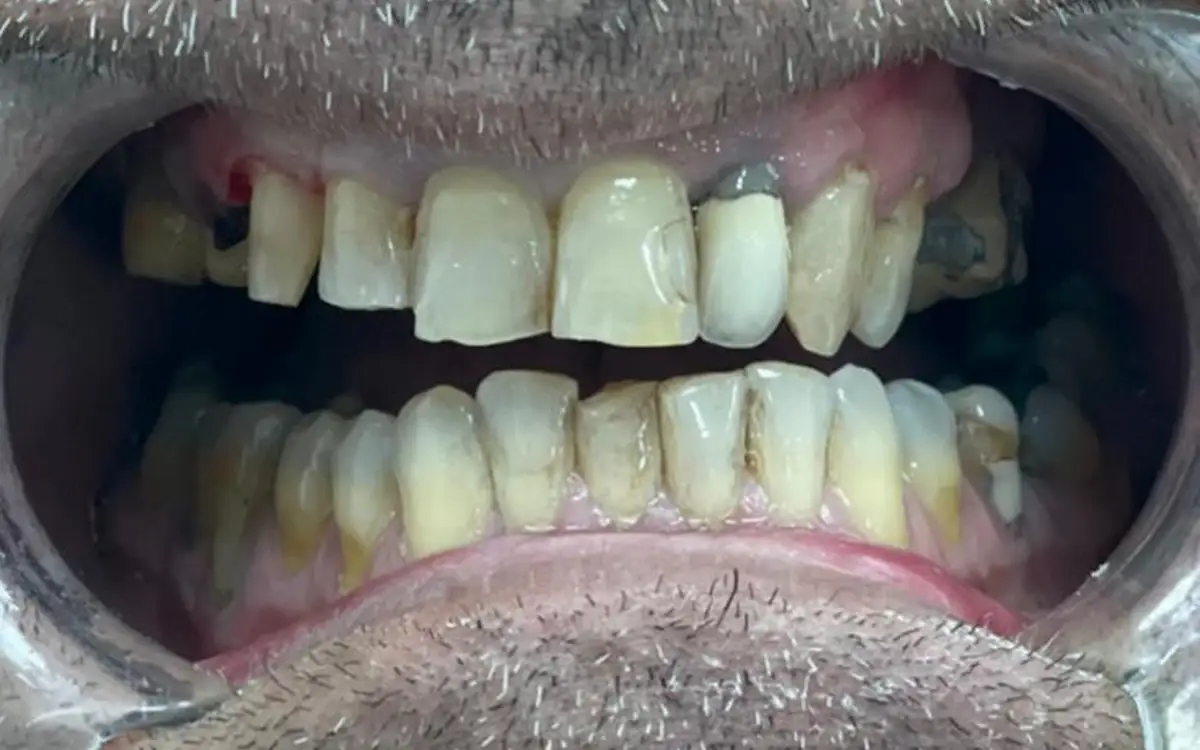

Smile After Smile Before

Smile After Before

Before dental treatment 1

Before dental treatment 2

Before dental treatment 3